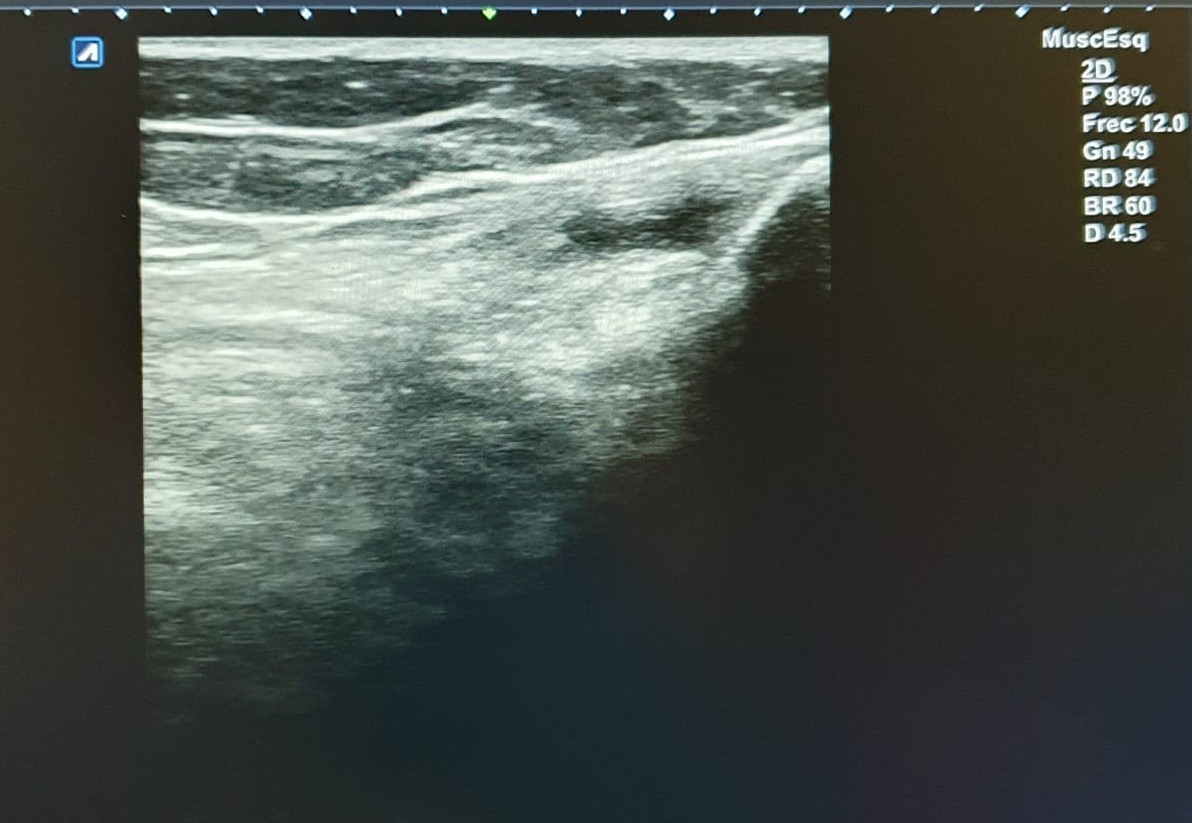

Hallazgos ecográficos

Ecografía de rodilla. Compartimento lateral: imagen anecoica/hipoecoica 10 x 5 mm en zona proximal de ligamento colateral lateral, sugestivo de rotura parcial. Compartimento posterior: imagen anecoica 20 x 30 mm sugestivo de quiste de Baker. No otras alteraciones ecográficas.